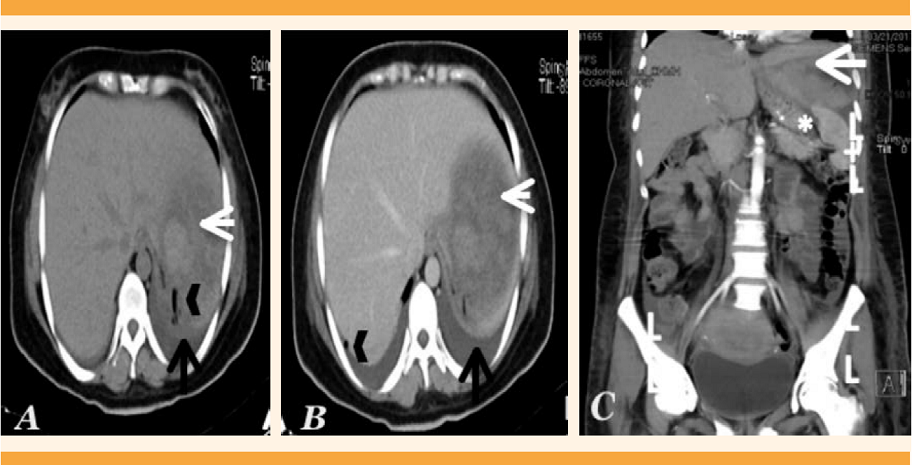

El ultrasonido de control al sexto día reportó: hígado con colección en el lóbulo izquierdo en relación con un hematoma en resolución, con volumen estimado de 36.8 mL, derrame pleural de predominio izquierdo. La tomografía simple y contrastada de abdomen identificó al hígado aumentado de tamaño en el lóbulo izquierdo, con densidad heterogénea a expensas de una imagen de forma irregular, bordes irregulares, con zonas hipodensas e isodensas en relación con el parénquima, localizada en el lóbulo hepático izquierdo, de aproximadamente 10 x 9 x 4 cm, bien delimitado por la cápsula hepática, que se advirtió íntegro. A la aplicación del medio de contraste no mostró reforzamiento y se descartó la hemorragia activa; la distribución de los vasos portales y hepáticos era congruente y sin evidencia de dilatación de la vía biliar. Figuras 1A y B.

Figura 1 Tomografía corte axial en fase simple (A) y venosa (B): Hematoma subcapsular (flecha blanca) en el lóbulo hepático de aproximadamente 10 x 9 x 4 cm. Aire libre intraabdominal por antecedente quirúrgico (punta de flecha). Derrame pleural bilateral (flecha negra). Tomografía coronal de abdomen (C): Hematoma subcapsular (flecha blanca) en el lóbulo izquierdo que desplaza el estómago (*) y bazo (+) en sentido caudal. Líquido libre (II) periesplénico y en ambas correderas parietocólicas.

Tomografía coronal de abdomen: hematoma subcapsular (flecha blanca) en el lóbulo hepático izquierdo que desplaza el estómago (*) y bazo (+) en sentido caudal. Líquido libre (ll) periesplénico y en ambas correderas parietocólicas. Figura 1C.